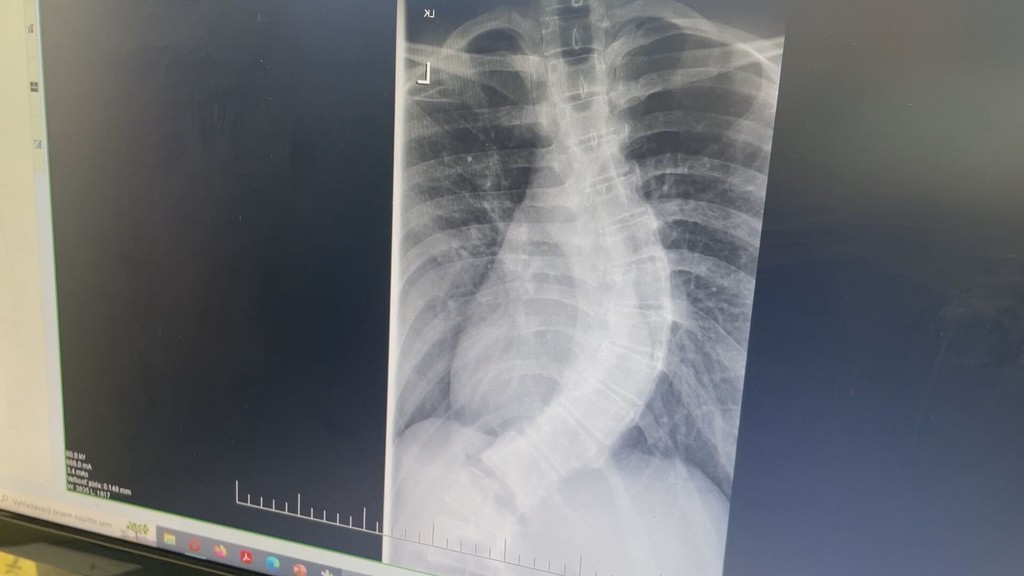

Ďalší úspech našich lekárov. S pomocou dvoch tyčí a 24 skrutiek narovnali 16-ročnému dievčaťu chrbticu

Trpezlivosť jej priniesla operáciu, vďaka ktorej bude ako ostatné dievčatá. Len 16-ročná Vladyslava mala mimoriadne vykrivenú chrbticu. Pôvodne bol jej zákrok plánovaný v deň, keď sa začala vojna u našich susedov, a tak našla riešenia až v novom útočisku.

Zakrivenie chrbtice bolo enormné, no vraj sú u mladých ľudí čoraz častejšie. Vladyslavu mali operovať v jej domovine, všetko bolo naplánované. Zákrok však zrušili a dievča z dokrútenou chrbticou utieklo aj s mamou za hranice. Dostali sa ku nám a tu aj začali zháňať liečbu.

Vykrivená chrbtica

Zdroj: TV Markíza

​Lekári chrbticu mladej pacientke museli vystužiť dvomi chróm-kobaltovými tyčami a utiahnuť 24 titánovými skrutkami.